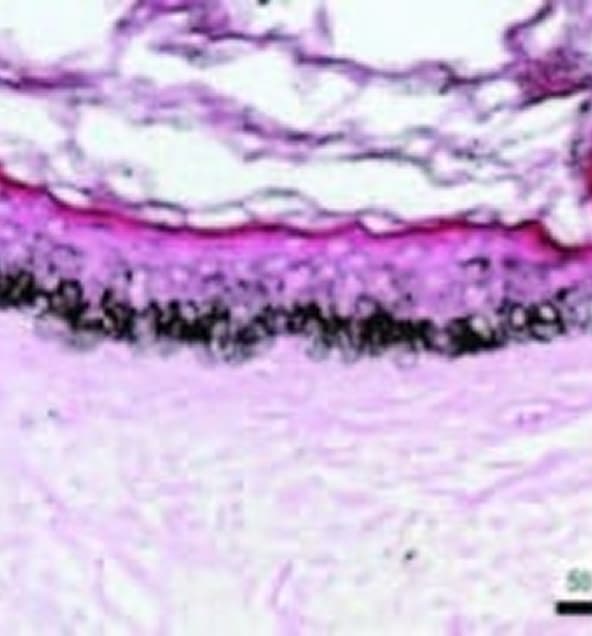

EPIDERMALE MELANINDICHTE BEI MELASMA VOR DEM EINGRIFF

REDUKTION DER EPIDERMALEN MELANINDICHTE 1 WOCHE NACH MIKRONEEDLINGVERFAHREN

- Induktion von Keratinozytenfluktuation und „Wiederherstellung“ der normalen Pigmentaktivität der Melanozyten in überpigmentierten Bereichen.

- Dies geschieht in der dermal-epidermalen Junktionszone (DEJ).

- Dieser Dermisbereich mit flacher DEJ ist die Zieltiefe für die Mikronadel. Siehe Pfeile, wo die Mikrokanäle gebildet werden